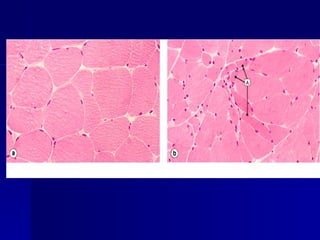

Hypertrophy - gross

Hypertrophy - micro

Myocardial hypertrophy

Cell Injury Cell Injury Hypertrophy- gross Hypertrophy - gross

Cell Injury Cell Injury Hypertrophy- micro Hypertrophy - micro